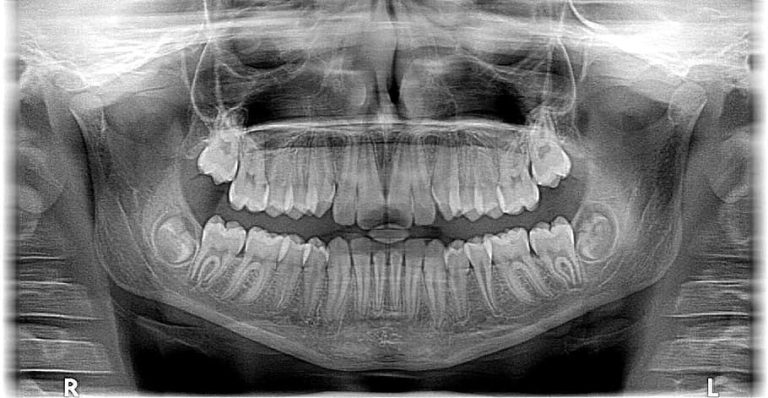

Paradontoza: cauze și efecte. De ce implantul dentar este soluția stabilă după căderea sau extragerea dinților?

Implant dentar sau punte dentară? Iată cum alegi corect și detalii de care trebuie să ții cont când iei decizia